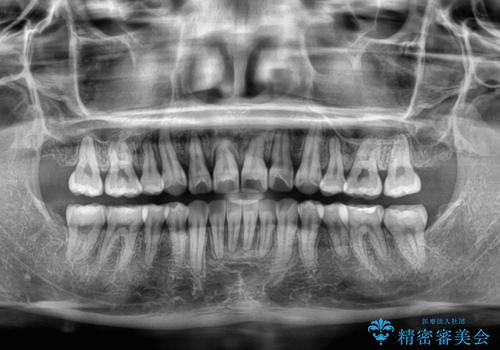

- 八重歯と、それによる正中のズレを気にして来院された患者様です。

口元の突出感は気にしていなかったため、上顎の左右第一小臼歯を抜歯することで、八重歯の解消と上顎の正中を改善していくこととしました。

奥歯の咬み合わせを維持しながら正中位置を改善するために、補助装置を使用しました。

予定より期間がかかりましたが、上下の正中位置を綺麗に一致させることができました。